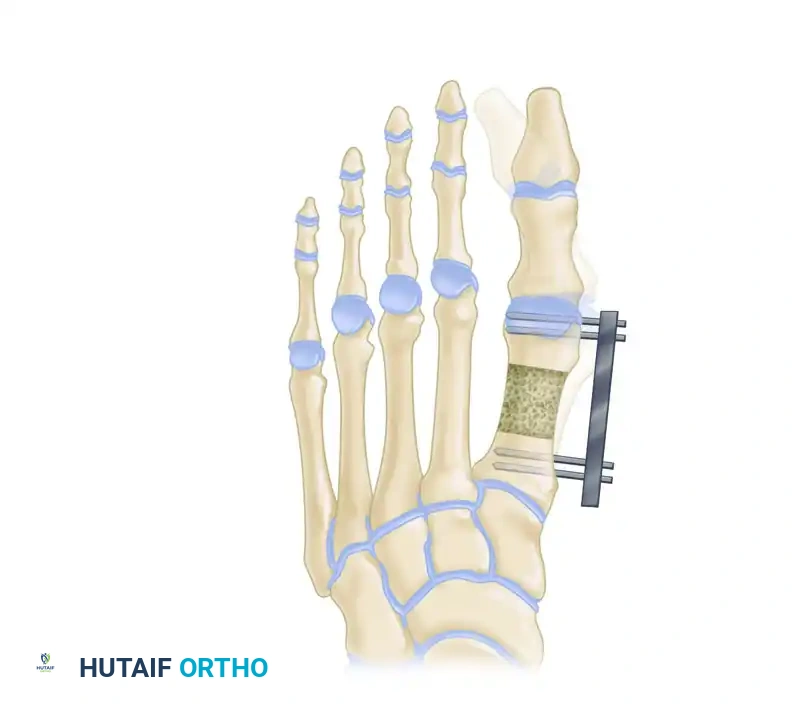

Distraction Osteogenesis (Callotasis)

For lengthening requirements exceeding 15 mm (or >40% of the native bone length), distraction osteogenesis is the gold standard. This technique, based on Ilizarov principles, allows for the gradual adaptation of the bone, skin, tendons, and neurovascular structures, significantly reducing the risk of acute ischemic complications.

Figure 9: External fixator application in the transverse plane. The fixator must be applied as parallel as possible to the axis of the second metatarsal to ensure a straight longitudinal distraction.

Figure 10: External fixator application in the sagittal plane. The rail must be parallel to the plantar surface of the foot to prevent iatrogenic elevation or depression of the metatarsal head.